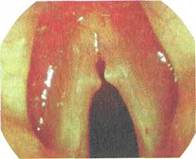

При ограниченной форме (певческие узелки) слизистая оболочка гортани розового цвета без особых изменений, на границе между передней и средней третями голосовых складок расположены симметричные образования в виде соединительнотканных выростов (узелков) на широком основании диаметром 1—2 мм. Эти узелки препятствуют полному смыканию голосовой щели, в результате чего голос становится хриплым (рис. 4.11).

Рис. 4.11. Ограниченная форма гиперпластического ларингита (певческие узелки).